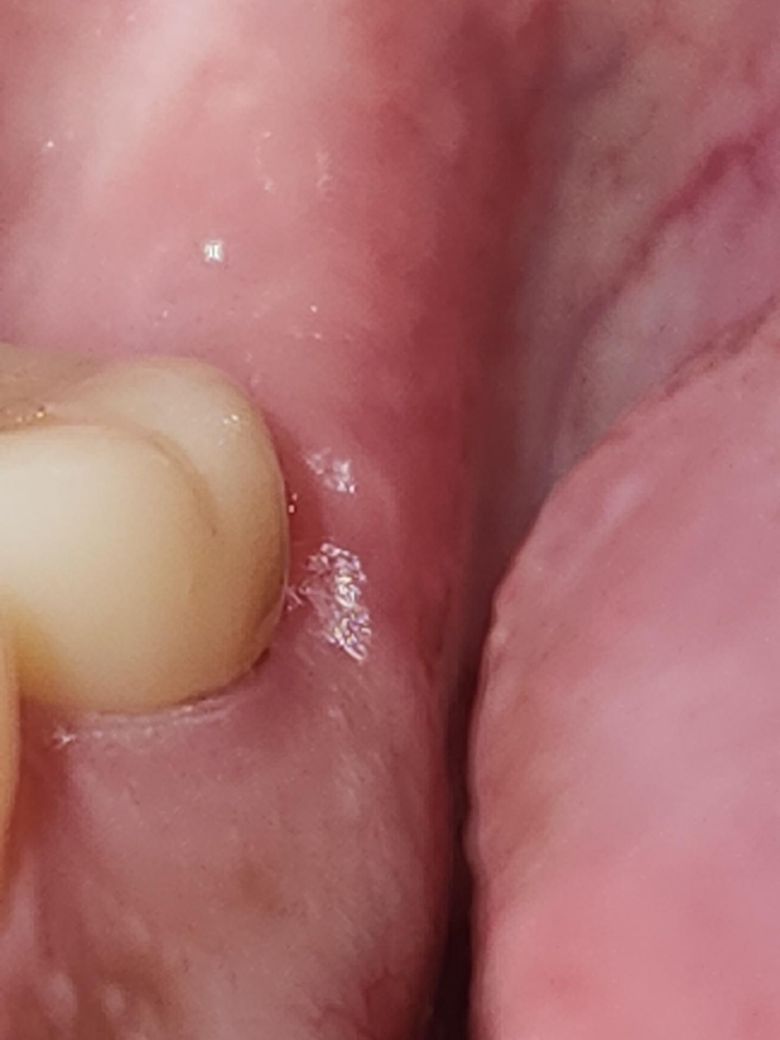

오늘 크라운을 부착했는데 크라운과 잇몸과 사이에 틈이 있는 것 같습니다.

오늘 크라운을 완전 부착하고 잠시뒤에 혀로 만쳐봤는데 안쪽 일부분에서 걸리는 느낌과 틈같은게 느껴졌습니다. 바로 다시 치과에가서 확인해달라고 했는데 대충 보고는 없다고하셔서 좀더 봐달라고 했지만 안해주셔서 어쩔 수 없이 집으로 돌아와 확인해보니 미세한 틈같은게 보였습니다. 괜찮은건가요?

저정도 틈은 시간이 지나면 잇몸이 차오르면서 메꿔집니다. 치아 삭제시 치아의 경계부위를 잘 나오기 하기 위해서 잇몸을 살짝 삭제를 하기도 합니다.

확인해보니 미세한 틈같은게 보였습니다. 괜찮은건가요? -> 사진상으로 미세한 간극이 보이긴 하는데 이정도면 잇몸이 회복되면서 높이가 맞춰질 것 같기도 합니다 1~2주정도 기다려보시기 바랍니다

보철물을 제작하고 부착하고 나면 보철물과 치아 사이에 경계면이 있을수 있습니다. 크게 문제가 되는 사항은 아니기 때문에 불편감이 없다면 걱정하지 않으셔도 될것으로 생각됩니다.